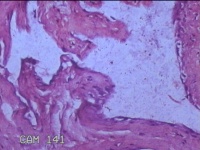

右侧髋部结节

性别

女

年龄

50岁

临床诊断

皮下结节

一般病史

发现右髋部结节1个月余。

标本名称

大体所见

灰白粉红色结节1.3x0.5x0.2cm一个,表面光滑,切开结节呈实性,切面灰白粉红色,质软。

图1

有的地方感觉像个血管瘤,未见明确恶性